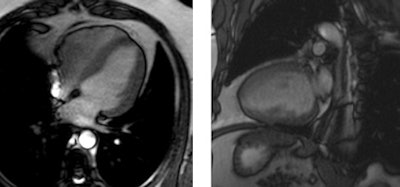

True fast imaging with steady-state precession (true-FISP) cine sequences were used to measure left and right ventricular dimensions and EF, and short-tau inversion recovery (STIR) sequences were used in a short axis stack. A dipyridamole (0.84 mg/kg) myocardial perfusion study was performed with gadolinium-DTPA (0.1 mmol/kg). Inversion-recovery sequences were used for detection of late gadolinium enhancement and T2-weighted turbo spin-echo sequences were used for the thoracic aorta.

End-diastolic volumes did not show differences with controls, according to Maceira, but end-systolic volumes were slightly enlarged (LV [left ventricle]: 31 ± 8 versus 24 ± 2 mL/m2, RV [right ventricle]: 38 ± 10 versus 28 ± 3 mL/m2, all p < 0.001) and so was the left ventricular mass index (80 ± 13 versus 69 ± 4 g/m2, p < 0.001). LV and RV ejection fraction (EF) were decreased compared with the controls (LV: 59 ± 6% versus 68 ± 4%, RV: 55 ± 5% versus 64 ± 6%, all p < 0.001).

About 35% of patients had decreased LVEF and 20% had decreased RVEF. About 29% of patients showed LV hypertrophy (14 concentric, 13 eccentric), and 12% presented concentric remodeling. No perfusion defects or necrosis patterns were seen, while 15 patients (26%) showed late gadolinium enhancement (one subendocardial, two subepicardial, 13 intramyocardial, and nine inferior ventricular junction).

"Cardiovascular MR at 3 tesla detected cardiovascular disease of variable degree in 69% of this cohort of consecutive cocaine abusers," Maceira concluded. "The main findings were a disease in systolic function of both left and right ventricles, an increase of left ventricular mass, and the presence of myocardial late gadolinium enhancement, suggestive of past myocarditis."